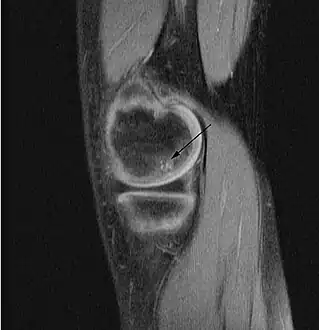

| A large flap lesion in the femur head typical of late stage Osteochondritis dissecans. In this case, the lesion was caused by avascular necrosis of the bone just under the cartilage. | |

Magnetic resonance imaging (MRI) is useful for staging OCD lesions, evaluating the integrity of the joint surface, and distinguishing normal variants of bone formation from OCD by showing bone and cartilage edema in the area of the irregularity. MRI provides information regarding features of the articular cartilage and bone under the cartilage, including edema, fractures, fluid interfaces, articular surface integrity, and fragment displacement.[37][38] A low T1 and high T2 signal at the fragment interface is seen in active lesions. This indicates an unstable lesion or recent microfractures.[30] While MRI and arthroscopy have a close correlation, X-ray films tend to be less inductive of similar MRI results.[38]

Sagittal MRI: Linear low T1 signal at the articular surfaces of the lateral aspects of the medial condyle of the femur confirms the presence of OCD.